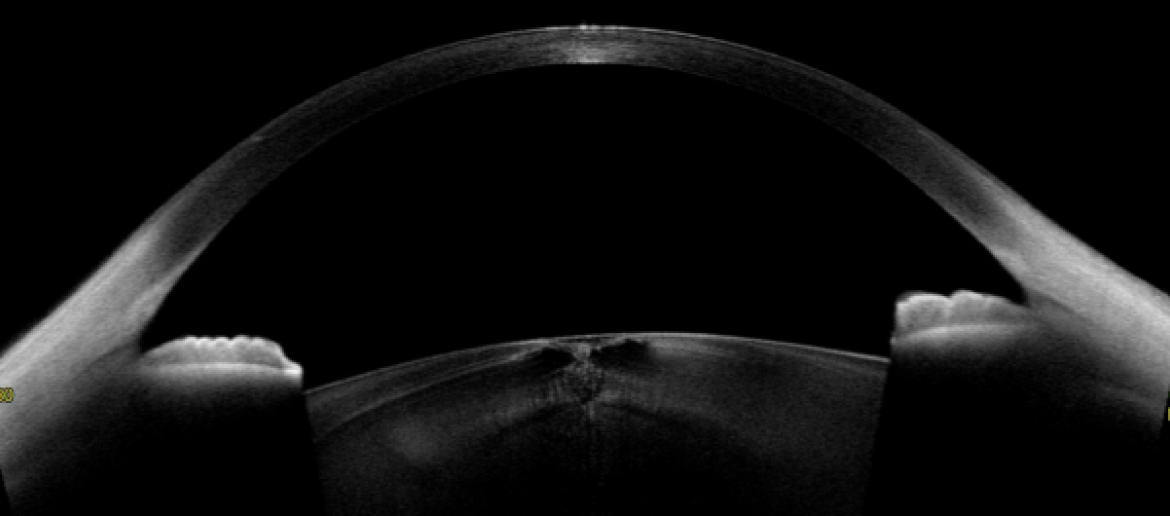

수술 후 안내렌즈(IOL)의 중심잡기와 기울임(Decenteration & Tilt)을

닥터 ICL 안과의 고해상도 CT “CASIA2”로 평가하는 모습

고기능 인공수정체(근시,원시,난시,노안 동시 교정, 3중초점, 4중 초점, 연속초점 IOL등) 는 안구 내 중심잡기와 기울어짐에 따라

같은 도수라도 시력의 질이 많이 차이가 날 수 있기 때문에 위 그림과 같은 측정이 꼭 필요합니다.

<고해상도 CT 의 진단으로 숨어있던 백내장을 찾아낸 실제 환자의 증례 사진 1,2>

시력저하 증상 때문에 불편해서 찾아간 외부병원 시력검사에서 1.0 가까이 시력이 나오고,

세극등검사 상에서 특이 소견이 없어서 안구건조증 치료만 하다가 의뢰된 분입니다.

진찰에서는 뚜렷하지 않던 백내장 소견이 고해상도 CT에서 수정체의 앞쪽 중심부(전낭하 피질혼탁)와

뒤쪽 중심부(후낭하 혼탁)에서 발견되었습니다.  크기가 작은 혼탁이지만,

시축(외부의 빛이 동공 중심부를 통해 시신경에 전달되는 직선거리)을 침범한 위치 상의 특징으로 인해 시력이 1.0 이 나오면서도

환자 분은 시각적인 불편함을 느끼는 경우로 자칫 간과되기 쉬운 미세혼탁백내장을 CT를 통해 진단한 사례입니다.